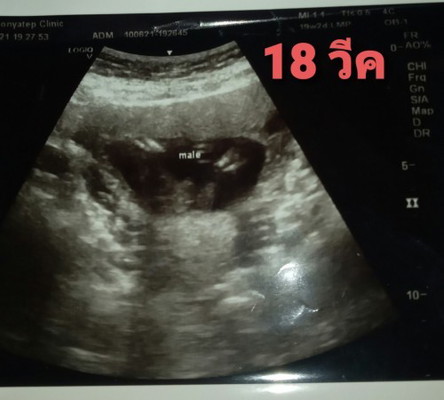

ซาวตอน18 วีคบอกผู้ชาย ซาวด์ตอน 20 วีค บอกผู้หญิง แม่ๆช่วยดูหน่อยค่ะ อันไหนจะน่าเป็นไปได้มากกว่ากัน😁 แต่เพศไหนแม่ก็ซีเรียส ค่ะ😉

( male )ได้ผู้ชายค่ะ บ้านนี้เพิ่งไปซาวด์ได้ชายเหมือนกันค่ะ